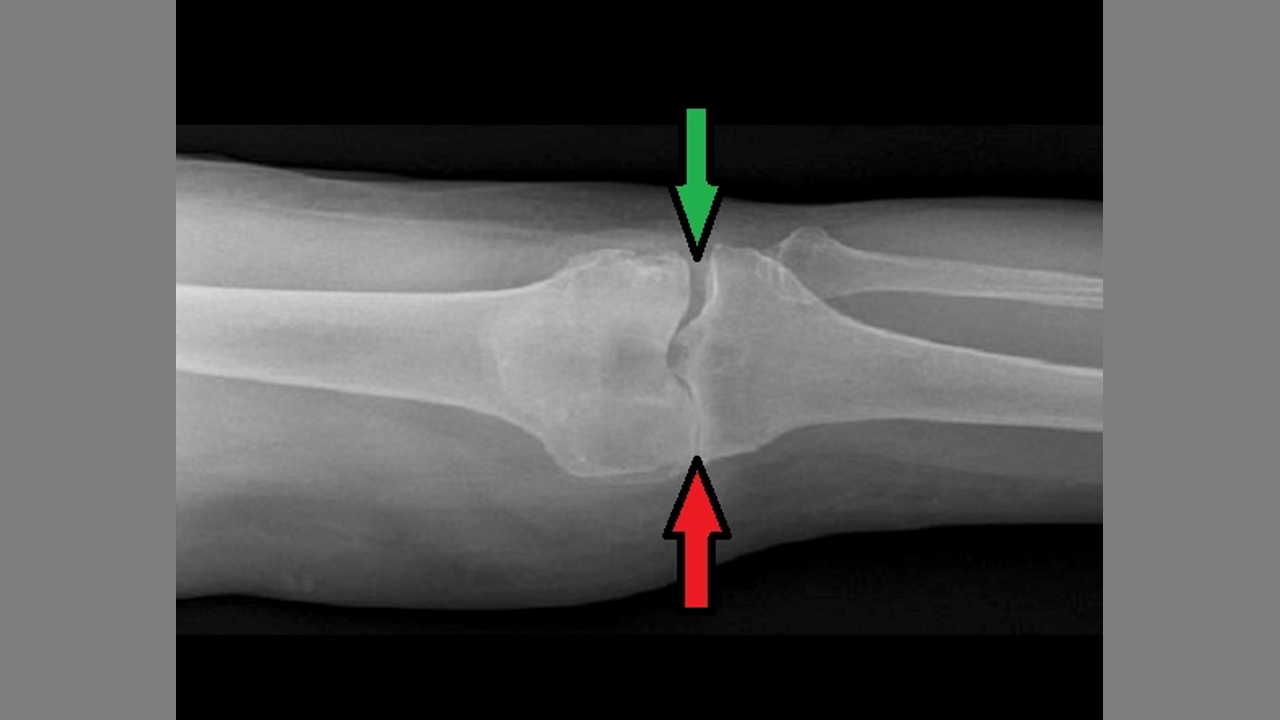

Tinnitus And Bone On Bone Knee Arthritis Dr Joel Wallach

Gary has tinnitus and bone on bone knee arthritis.